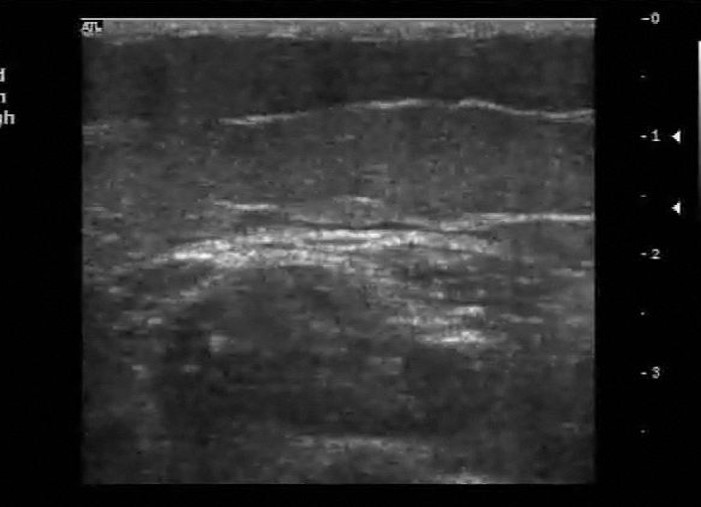

what is a baker’s cyst?

collection of synovial fluid that leaks from the knee joint

where is a baker’s cyst found?

A popliteal baker’s cyst is usually what shape?

crescent shaped